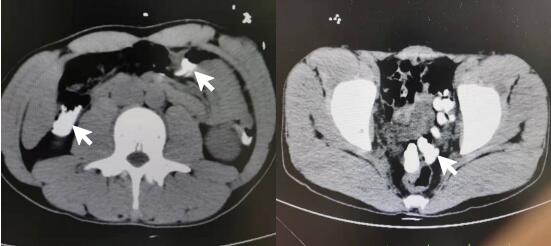

1 资料与方法患者男性,24岁,工人,因感情问题情绪失控后口服磷酸铵盐灭火剂,未混合其他液体,干粉直接吞服,具体剂量难以准确估计,数分钟后出现呕吐伴口咽部疼痛。约3h后到达外院洗胃,洗出大量黏稠浑浊液体。后留置胃肠减压,缓慢引流出灭火剂混合淡褐色胃液。胃液隐血++,血白细胞21.1×109/L,肌酸激酶2 006 U/L,动脉血气分析pH 7.26,标准碳酸氢根15.1 mmol/L,碱剩余-12.4 mmol/L,血钾5.6 mmol/L,血钙1.06 mmol/L。立位腹部平片及胸部CT平扫见胃腔内大量高密度影(见图 1)。外院给予护胃、纠正酸中毒及补液对症治疗,后转至本院进一步就诊。

| 图 1 患者外院立位腹部平片和胸部CT平扫示胃腔内大量高密度影 |